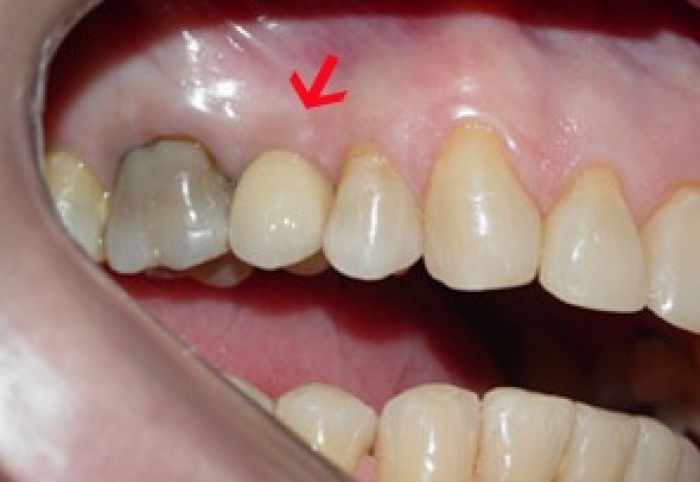

Prótese fixa sobre implante do caso terminado em fevereiro de 2009